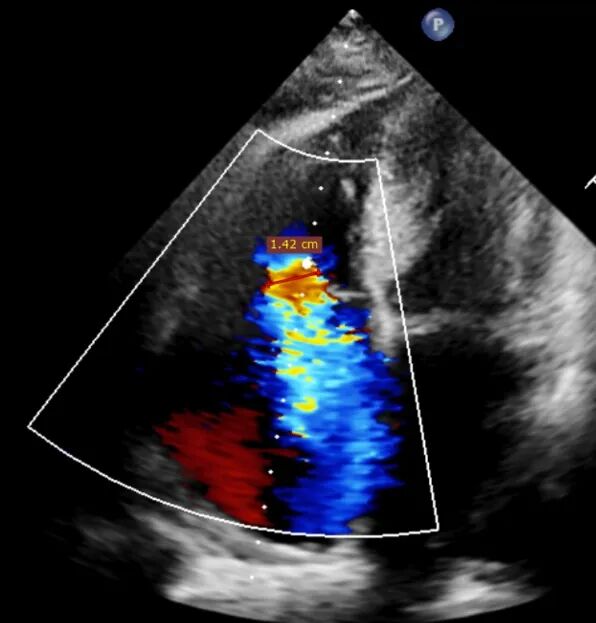

Preoperative echocardiographic evaluation: severe tricuspid regurgitation (grade 5+).

1. Preoperative baseline regurgitation

Regurgitation assessment: Regurgitation severity reduced from preoperative 5+ to 1+.